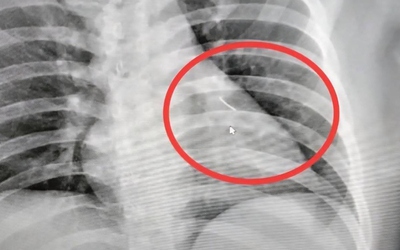

Người phụ nữ 25 tuổi ho dữ dội, bác sĩ sốc nặng khi phát hiện bí mật "đáng sợ"

Sức khỏe Thứ 2, 25/05/2026 | 10:20

Ban đầu cô gái trẻ cho rằng những cơn ho là do hít phải lông chó. Nhưng sau đó, cô đã rất sốc khi phát hiện ra "thủ phạm" thực sự.